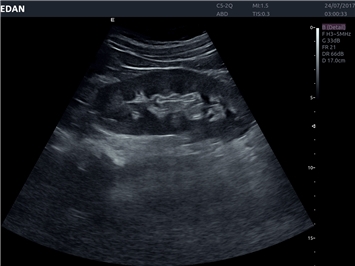

EDAN Acclarix LX4

Расширьте свои представления. Использование усовершенствованной платформой Acclarix система LX4 обеспечивает непревзойденную четкость изображений и интеллектуальный рабочий процесс для всех пользователей, являясь при этом наиболее экономичным решением.

EDAN Acclarix LX4 представляет собой инновационную ультразвуковую систему, построенную на усовершенствованной платформе Acclarix. Сочетание высокого качества визуализации с интеллектуальным рабочим процессом делает эту систему оптимальным выбором для клиник, ценящих эффективность и экономичность.

• Акушерства и гинекологии